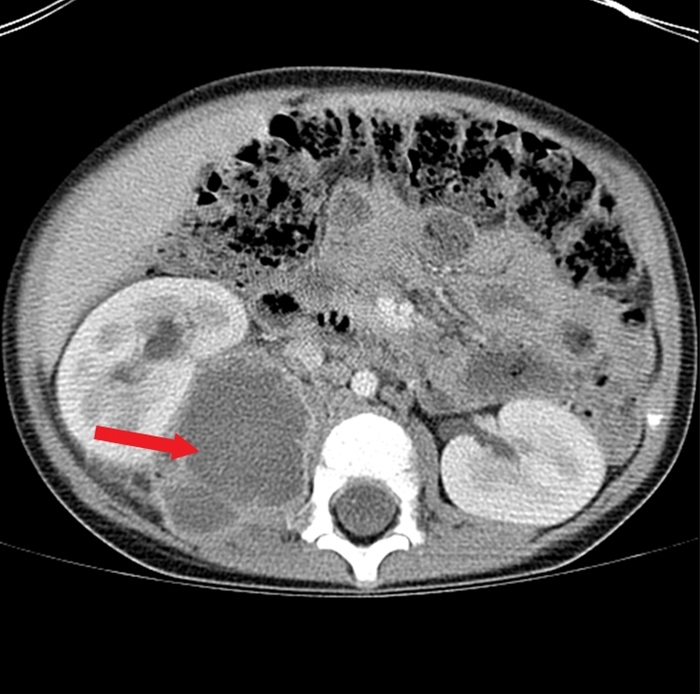

This patient with a recent history of skin infection who presents with fever and abdominal pain radiating to the groin likely has a psoas abscess (PA). PA occurs from either hematologic seeding from a distant infection or from direct extension of an intraabdominal infection (eg, diverticulitis, vertebral osteomyelitis). Risk factors include HIV, intravenous drug use, diabetes, and Crohn disease.

PA frequently presents subacutely with fever and lower abdominal or flank pain, although symptoms (eg, anorexia, weight loss) can be nonspecific. Consequently, PA should be considered as part of the evaluation for fever of unknown origin. Deep abdominal palpation is required to elicit tenderness due to the location of the psoas on the posterior abdominal wall. The "psoas sign," abdominal pain with hip extension, can often be detected on examination. Laboratory studies commonly show leukocytosis, thrombocytosis, and elevated inflammatory markers. CT scans are required to confirm the diagnosis. Drainage is critical, and blood and abscess cultures should be obtained to guide antibiotic therapy.